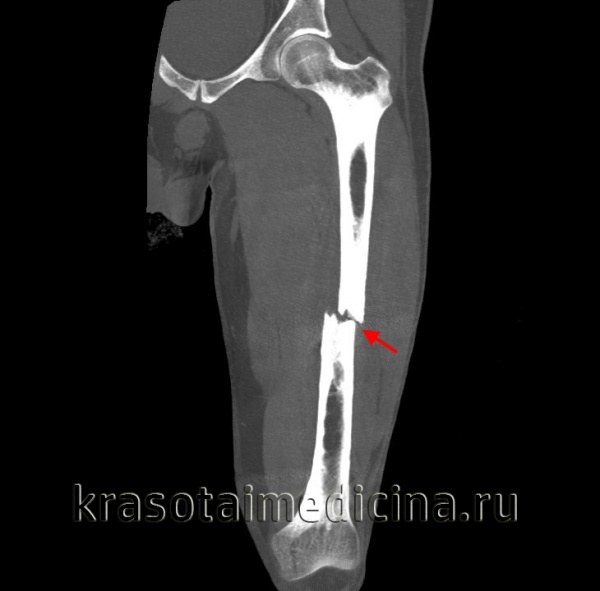

Признаки перелома головки бедренной кости

Перелом головки бедренной кости. Диагностика и лечение

В этой и последующих статьях на сайте будут рассмотрены переломы головки, шейки, вертелов и диафиза бедренной кости до 5 см дистальнее малого вертела. Основное внимание уделено наиболее часто диагностируемым переломам и их лечению.

Для выявления переломов этого типа достаточно, как правило, обычных рентгенограмм в прямой проекции и в проекции с наружной и внутренней ротацией бедра. Диагностике скрытых переломов часто помогают рентгенограммы в сравнительных проекциях. У всех больных с подозрением на перелом бедра должна быть тщательно изучена линия Шентона. Кроме того, при подозрении на перелом необходима оценка шеечно-диафизарного угла, который в норме составляет 120—130°. Его измеряют от точки линий пересечения, проведенных по осям диафиза и шейки бедренной кости.

Класс А: перелом головки бедренной кости

Перелом головки бедренной кости встречается редко и может проявиться в сочетании с вывихом или без какой-либо значительной деформации. Его классифицируют по двум типам на основании размера и количества фрагментов. При переломах I типа имеется один фрагмент, в то время как переломы II типа являются оскольчатыми.